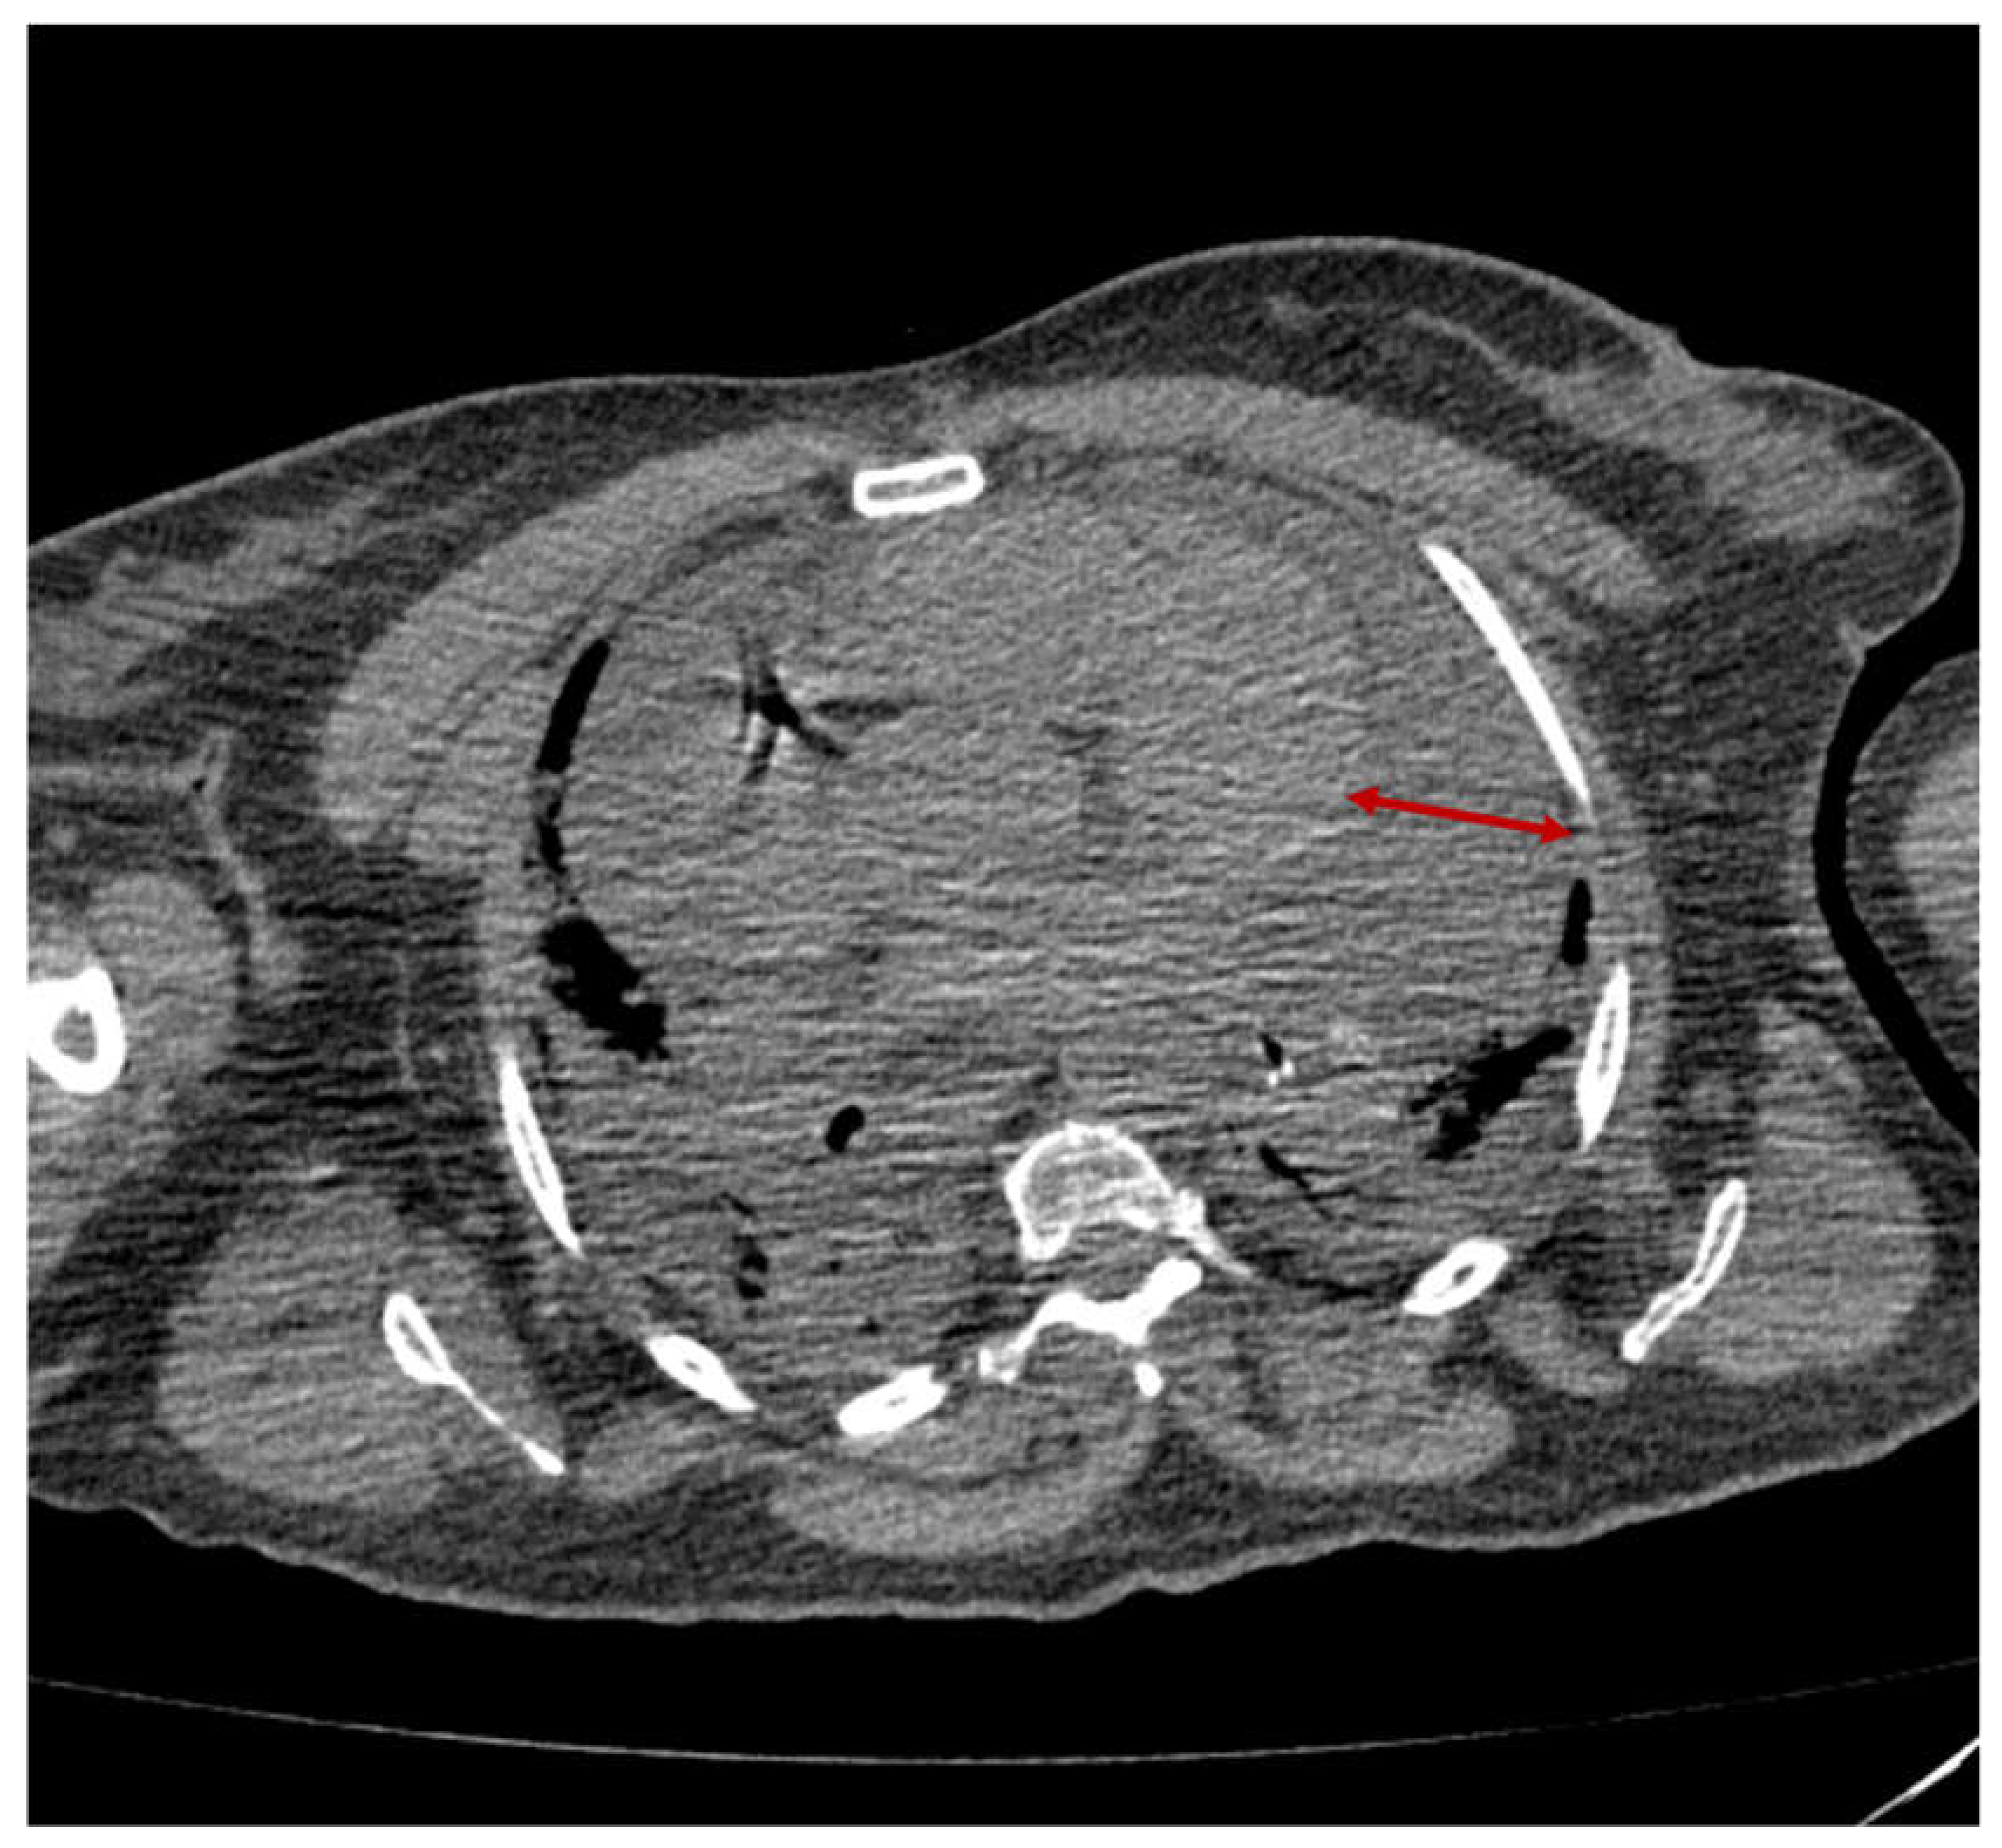

2.1. Case 1

2.2. Case 2

2.3. Case 3

2.4. Case 4